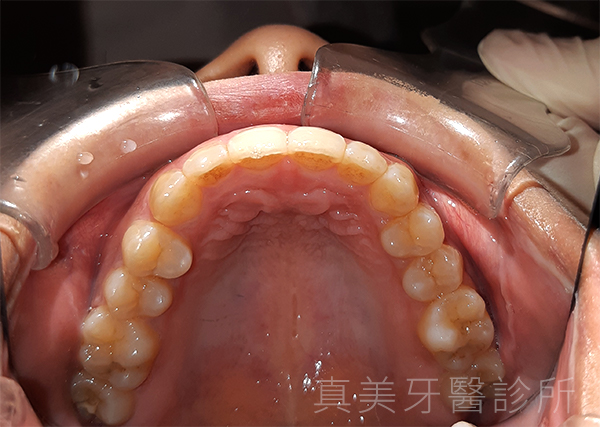

經過療程後,洪小姐的牙齒排列整齊了許多,原本外凸的門牙消失了,牙弓也變得更寬更自然。她開心地說,現在不但更喜歡照鏡子,也在合照時勇敢露齒微笑,甚至開始更積極參與各種社交場合。